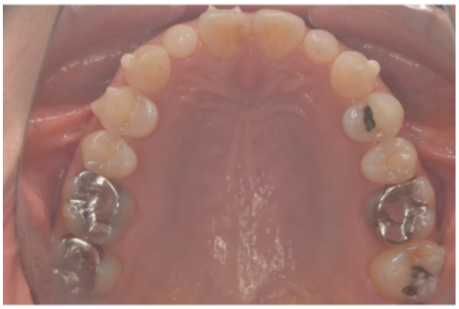

セラミック 2021.0930代女性「銀歯をすべて白くしたい」E-maxセラミックと保険のレジンで白くした症例